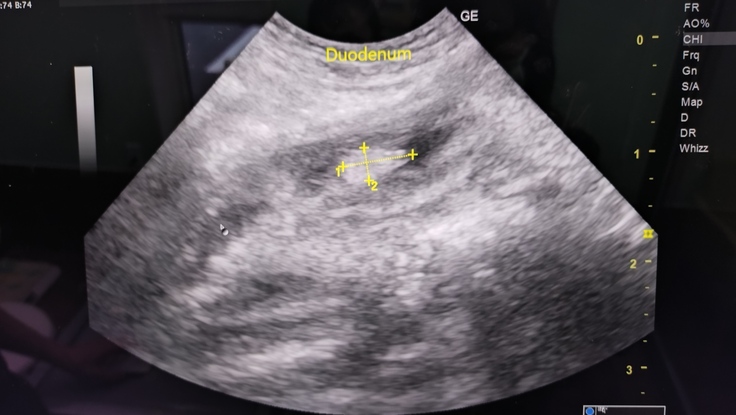

腎盂腎炎疑い一昨日の採血では腎臓肝臓の数値は問題ないので、可能性としては低いが、エコーで見ると拡張してくるので確認。エコー所見で腎盂腎炎はなし。

腹水がまた溜まってる。

エコーの白みはそこまで強くはないが、また腹膜炎が起きている可能性が高い。